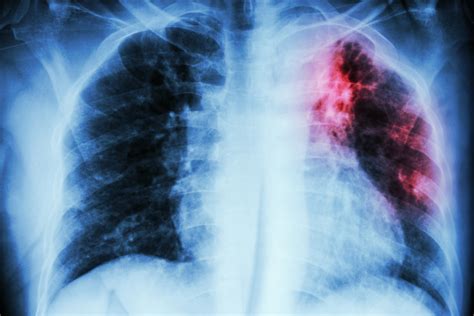

Interpreting Tb X Ray results requires expertise and experience. Radiologists look for specific signs that may indicate TB:

• Cavities: These are hollow spaces in the lungs that can form as the body tries to contain the infection.

• Nodules: Small, round opacities that can be indicative of TB infection.

• Infiltrates: Areas of increased density in the lung tissue, often seen in active TB.

• Pleural Effusion: Fluid accumulation in the pleural space, which can be a complication of TB.